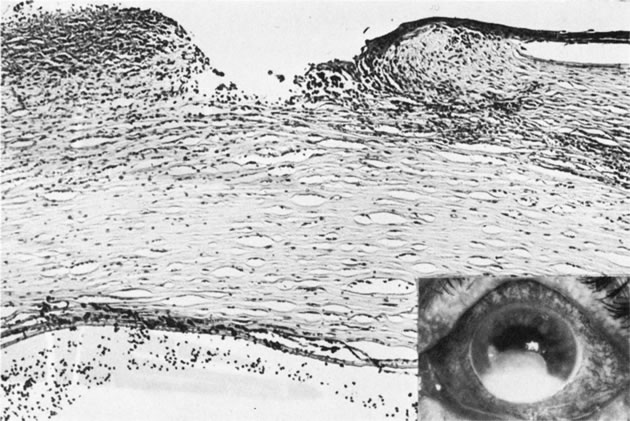

PETERS' ANOMALY

Peters' anomaly includes absence of central corneal endothelium, Descemet's membrane, and variable amounts of corneal stroma (Fig. 4). In most cases Bowman's membrane also is absent. Peters' anomaly may be caused by primary dysgenesis of the corneal endothelial mesoderm, primary dysgenesis of keratocyte and endothelial neural crest mesoderm, or secondary endothelial degeneration due to late anterior displacement of a normally developed crystalline lens.48 In addition, it has been suggested that abnormal apposition of an ectopic lens to the developing cornea during the second or third month of gestation may be the cause of exceptional cases of peripheral Peters' anomaly.49

Fig. 4. Peters' anomaly. A. Note the central corneal scar in the right and left eyes. The lens was adherent to the back of the corneal scar. Iris abnormalities also were present. B. The anterior segment shows a posterior corneal defect, a “top hat” appearance of the lens, and total adherence of the anterior surface of the iris to the cornea. C. High magnification shows termination of the endothelium and Descemet's membrane (arrow), corneal thinning, and localized absence of Bowman's membrane. The lens (lower left) is artifactually separated from the cornea. D. A PAS-positive membrane (lens capsule) is shown (top) adherent to the posterior corneal surface (arrow). The lens cortex (c) is artifactually separated from the rest of the lens (bottom). (Courtesy of SEI Photoarchives.) (B–D modified from Scheie HG, Yanoff M: Peter's anomaly and total posterior coloboma of retinal pigment epithelium and choroid. Arch Ophthalmol 87:525, 1972.)

Associated anterior segment anomalies include corectopia, iris hypoplasia, anterior polar cataract or other lens abnormalities, and iridocorneal adhesion. (Fig. 5) Corneal perforations secondary to Peters' anomaly have been reported at birth.50,51 Systemic anomalies include Potter's syndrome (agenesis of the urinary tract) and intestinal malrotation.52–54 Generally, no specific inheritance pattern has been noted, although a family that had an autosomal dominant inheritance pattern has been reported.55

Fig. 5. Peters' syndrome complicated by buphthalmos. The corneal anterior segment of the right eye has expanded because of the influence of increased intraocular pressure on scleral tissue that is still elastic in young people.

Histopathologic findings include absence of Descemet's membrane, corneal endothelium, and usually Bowman's membrane, as well as thinning of corneal stroma. The defects in Descemet's membrane, although usually single and central, may be multiple and isolated to the periphery or may be limited to an area of adhesion of iris.56 Descemet's membrane has been found to have embryonal ultrastructural characteristics combined with attenuated endothelium.57 The corneal stromal lamella are more irregular and closely packed when compared with normal. Immunohistochemical markers indicate that a normal complement of collagens type I, III, IV, V, and VI occurs in Peters' anomaly; however, an increased concentration may occur of the adhesive protein fibronectin, which is known to play a role in the embryologic development of the cornea.58–60